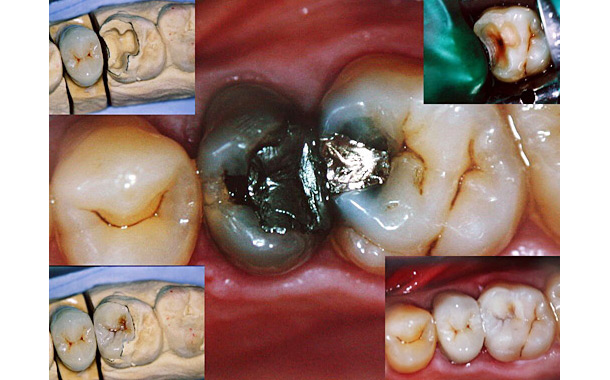

Avec les illustrations photographiques suivantes, vous pourrez voir comment cela se passe plus précisément: La dent initialement malade, puis la préparation de celle-ci, et enfin la mise en place de l’inlay esthétique venant combler le trou dans la dent.